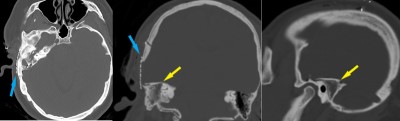

This is a 28 year old female who presents with complaint of right-sided hearing loss and sense of fullness within her right ear.

Her exam is consistent with conductive hearing loss in right ear.

Intraoperative photo demonstrating the operative approach. A right temporal craniotomy has been made and the covering of the brain, the dura mater, is being dissected off of the base of the skull. Orientation: this is the right side of the head; the ear is just off the top of the frame (green star(*)), the nose is to the left, the back of the head the right, and the top of the head is toward the bottom.